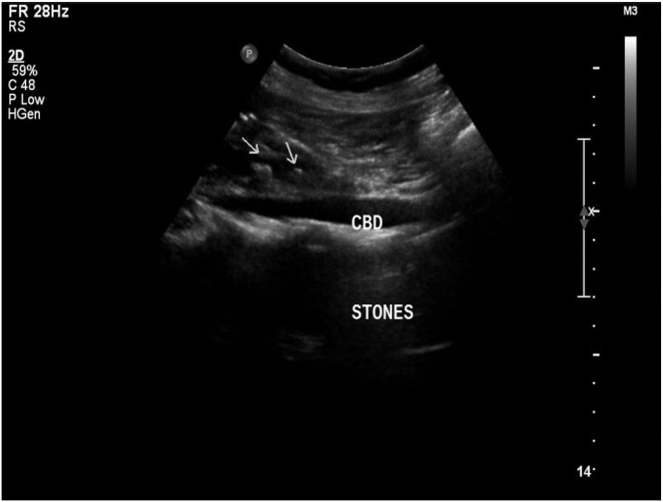

Herein we report a case of a 50-year-old woman presented with epigastric and left upper quadrant pain. Preoperative examination revealed abnormal liver chemistries, situs inversus totalis, and multiple distal common bile duct stones with intrahepatic and extrahepatic bile duct dilatation on abdominal ultrasound. The patient underwent a successful ERCP to relieve biliary obstruction. It was performed while the patient was placed in a supine position with the endoscopist standing on the left side of the patient.